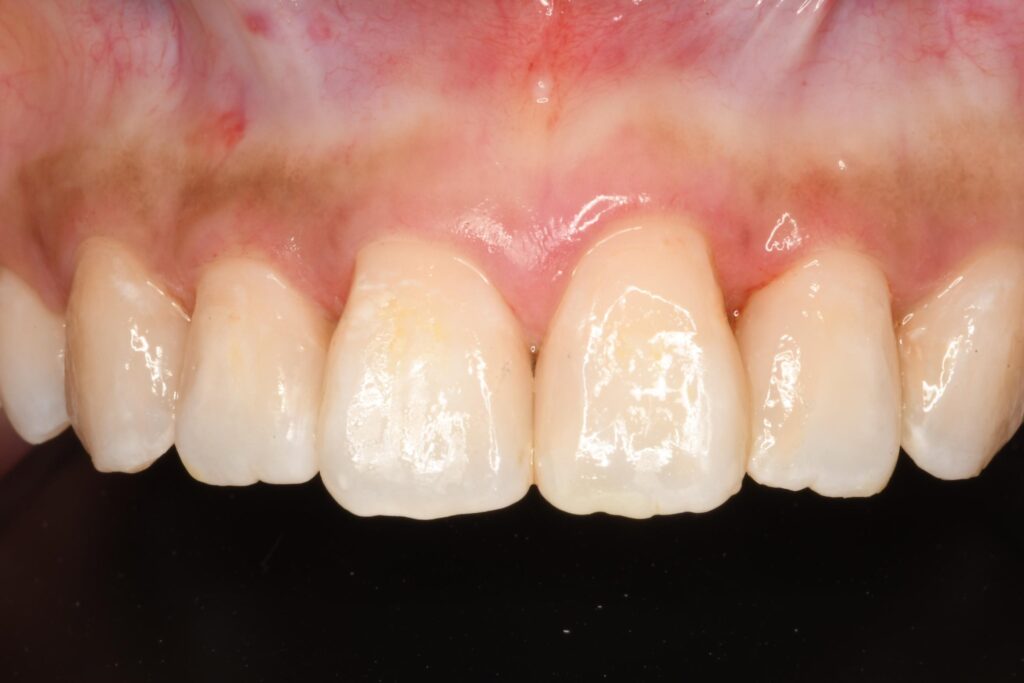

前歯に約10か所のレジン修復と変色

【治療前の写真:歯と歯の間に樹脂の変色が見られる。】

診察すると、前歯部に約10か所のコンポジットレジン(CR)修復があり、境目の着色や全体の変色が気になる状態でした。

コンポジットレジンは歯を削る量を抑えながら自然な見た目を作れる一方で、時間とともに表面の細かな傷や段差に着色が入り、色のズレが目立ってくることがあります。